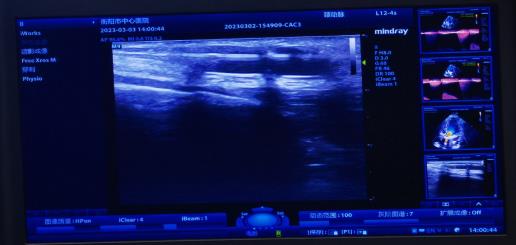

腎內(nèi)科通訊員黃佩君報(bào)道:來(lái)自衡陽(yáng)縣的謝奶奶2年前因尿毒癥開(kāi)始行維持性血液透析維持生命,1周前內(nèi)瘺流量明顯下降,不能滿足透析需要,慕名來(lái)到我院腎內(nèi)科就診。彩超檢查提示內(nèi)瘺口至內(nèi)瘺口近心端有約2.5cm管腔狹窄,經(jīng)綜合評(píng)估后,腎內(nèi)科陳鐵領(lǐng)副主任、彩超室王勝利副主任醫(yī)師、腎內(nèi)科王靜醫(yī)師給予患者實(shí)施彩超引導(dǎo)下動(dòng)靜脈內(nèi)瘺狹窄球囊擴(kuò)張術(shù),短短20分鐘便完成手術(shù),術(shù)后患者內(nèi)瘺震顫明顯,流量大幅增加。

動(dòng)靜脈內(nèi)瘺球囊擴(kuò)張術(shù)(PTA),通俗地講就是在超聲引導(dǎo)下,通過(guò)經(jīng)皮穿刺血管,置入導(dǎo)絲,沿導(dǎo)絲將高壓球囊送至血管狹窄/栓塞病變處,然后使用壓力泵打開(kāi)球囊,將狹窄/栓塞的病變擴(kuò)張開(kāi)的過(guò)程。它的優(yōu)勢(shì)非常明顯,不僅手術(shù)創(chuàng)面小(無(wú)切口,僅為一穿刺點(diǎn)),失血少,安全有效,可反復(fù)進(jìn)行,術(shù)后即可使用,不需中心靜脈靜脈導(dǎo)管過(guò)渡,患者舒適無(wú)痛苦,最重要的節(jié)省保護(hù)了患者的血管資源,可確保透析順利進(jìn)行。是目前動(dòng)靜脈內(nèi)瘺狹窄/栓塞首選治療方法。